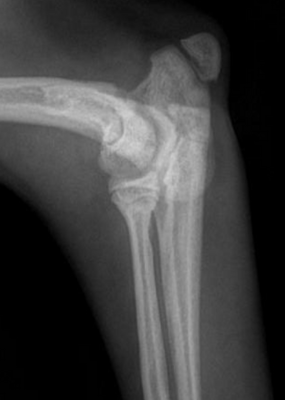

2. Radiographies du coude

Souvent le premier examen réalisé. Elles peuvent révéler :

- une fine ligne radiotransparente entre les condyles huméraux

- Une réaction périostée sur la crête épicondylaire latérale

- des signes d’arthrose précoce.

Plusieurs vues sont réalisées comprenant une face classique craniocaudal, une vue latérale en flexion, une vue oblique craniomédiale à caudolatérale avec une rotation de 15 degrés.

Cependant, la fissure peut être trop fine pour être visible.